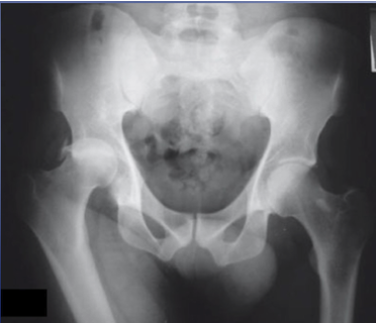

What is shown on this X-ray?

Hip dislocation